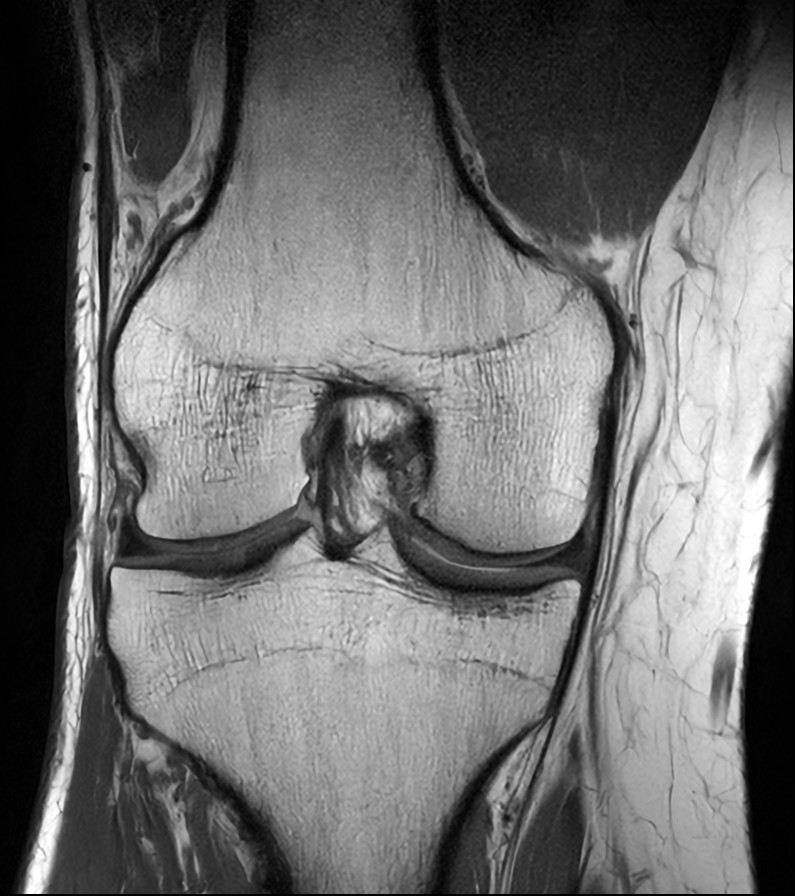

Fast Knee imaging with SmartSpeed Precise